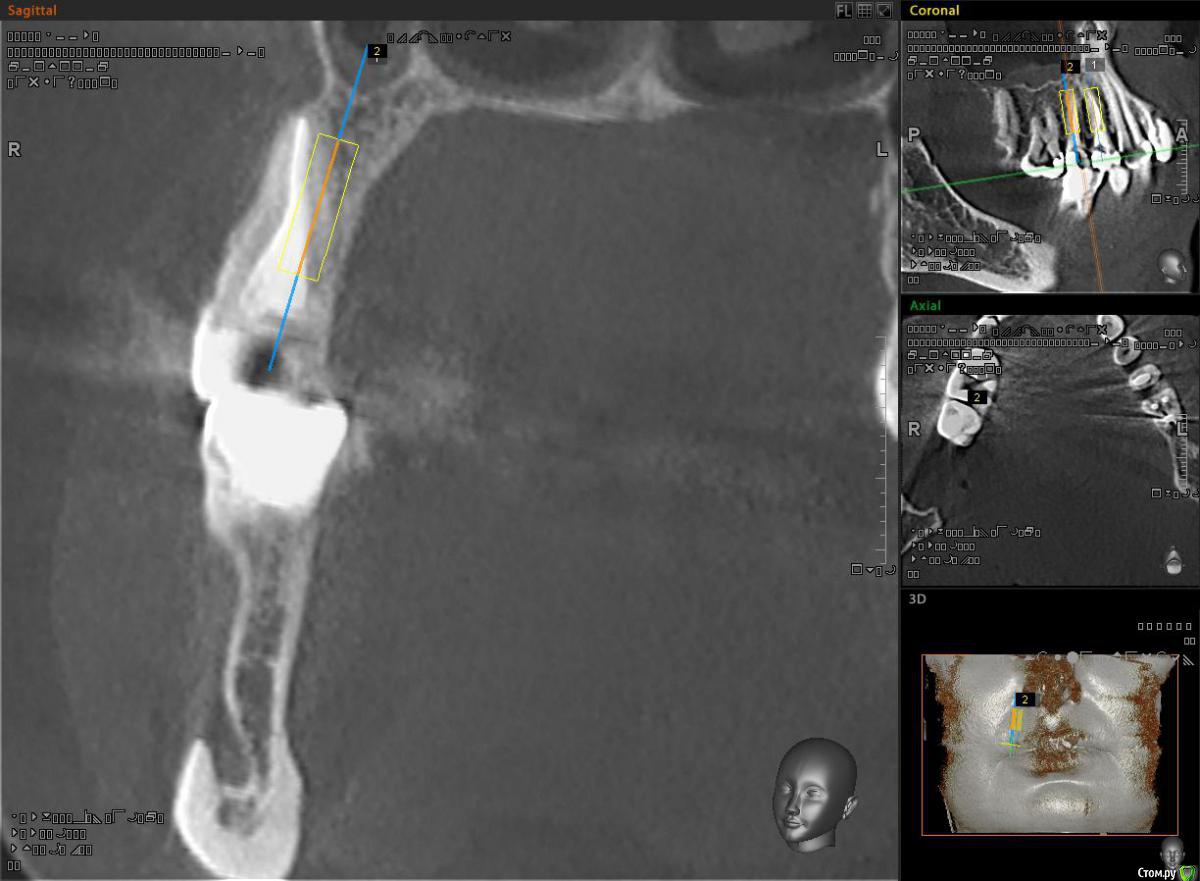

alekszander Опубликовано 3 ноября, 2015 Поделиться Опубликовано 3 ноября, 2015 Всем доброго времени суток! Снова нужна помощь коллеги.Пациентка направлена на ортопедию от врача терапевта. Ситуация - тотальный дефект зубы 1.5.1.4. Сохранить можно только на ЛКШВ(чего я не люблю .Согласна на имплантаты, НО - дефицит места как по высоте(относительно для одомоментной), так и по апроксимальным контактам. Имлантаты виртуально выставил 3.3х10. Длинее в 1.4 не поставить, апекс клыка мешает. Зуб 1.5 можно и 12мм. Смущает места между имплантатами и место до корней зубов. Между винтами ~2.5 мм. до корней ~1.5-2 мм. Что посоветуете? как сами поступаете в таких случаях? Ссылка на комментарий

alekszander Опубликовано 4 ноября, 2015 Автор Поделиться Опубликовано 4 ноября, 2015 Спасибо за советы.1. Для Diesel87(простите имени не знаю). Да я хирург. Здесь все срезы выставить не могу, но максимум там проходят 3.3 чтобы потом нормально запротезировать. Бикортикально не хочу, т.к. в наличии только мис и адин, а у них агресивный апекс, есть риск. А насчет длины согласен можно и длинее. 2. Карен, Александр. Вот и у меня сомнения. Но там нужна реэндодонтия,ЛКШВ,клин. удлинение, и только потом постоянные коронки. По срокам и цене получится чуть дешевле имплантации.Вот и задумываюсь что лучше. Ссылка на комментарий